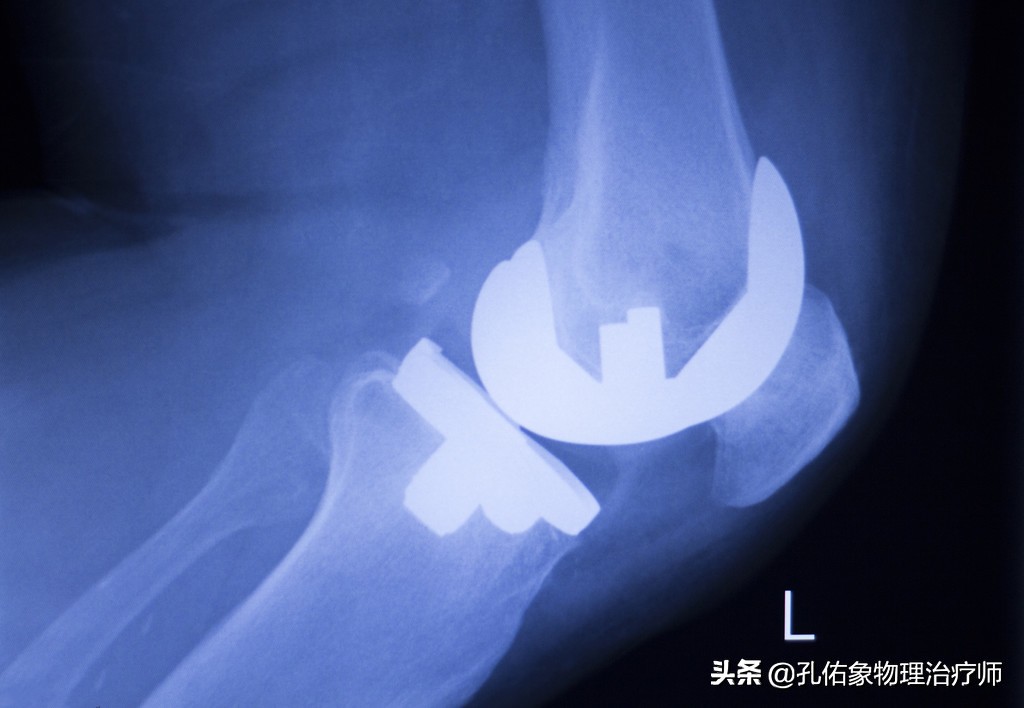

膝痛在早期时,往往只体现出局部的疼痛,局部的炎症肿胀;但是随着自身的不注意,慢慢的力学改变,膝盖骨与大腿骨撞击就会引起膝盖骨下面的软骨损伤,逐年累月的血液循环障碍、骨质增生、骨赘形成;到这个时候要解决问题,只有通过手术,关节镜下处理或是直接用一个假的膝关节换进去。

我目前接诊着一个病人,还是医务工作者,才年仅42岁呀,就把膝关节给换了;因为我上面所写的的,在她身上都可以淋淋尽致的体现出来。